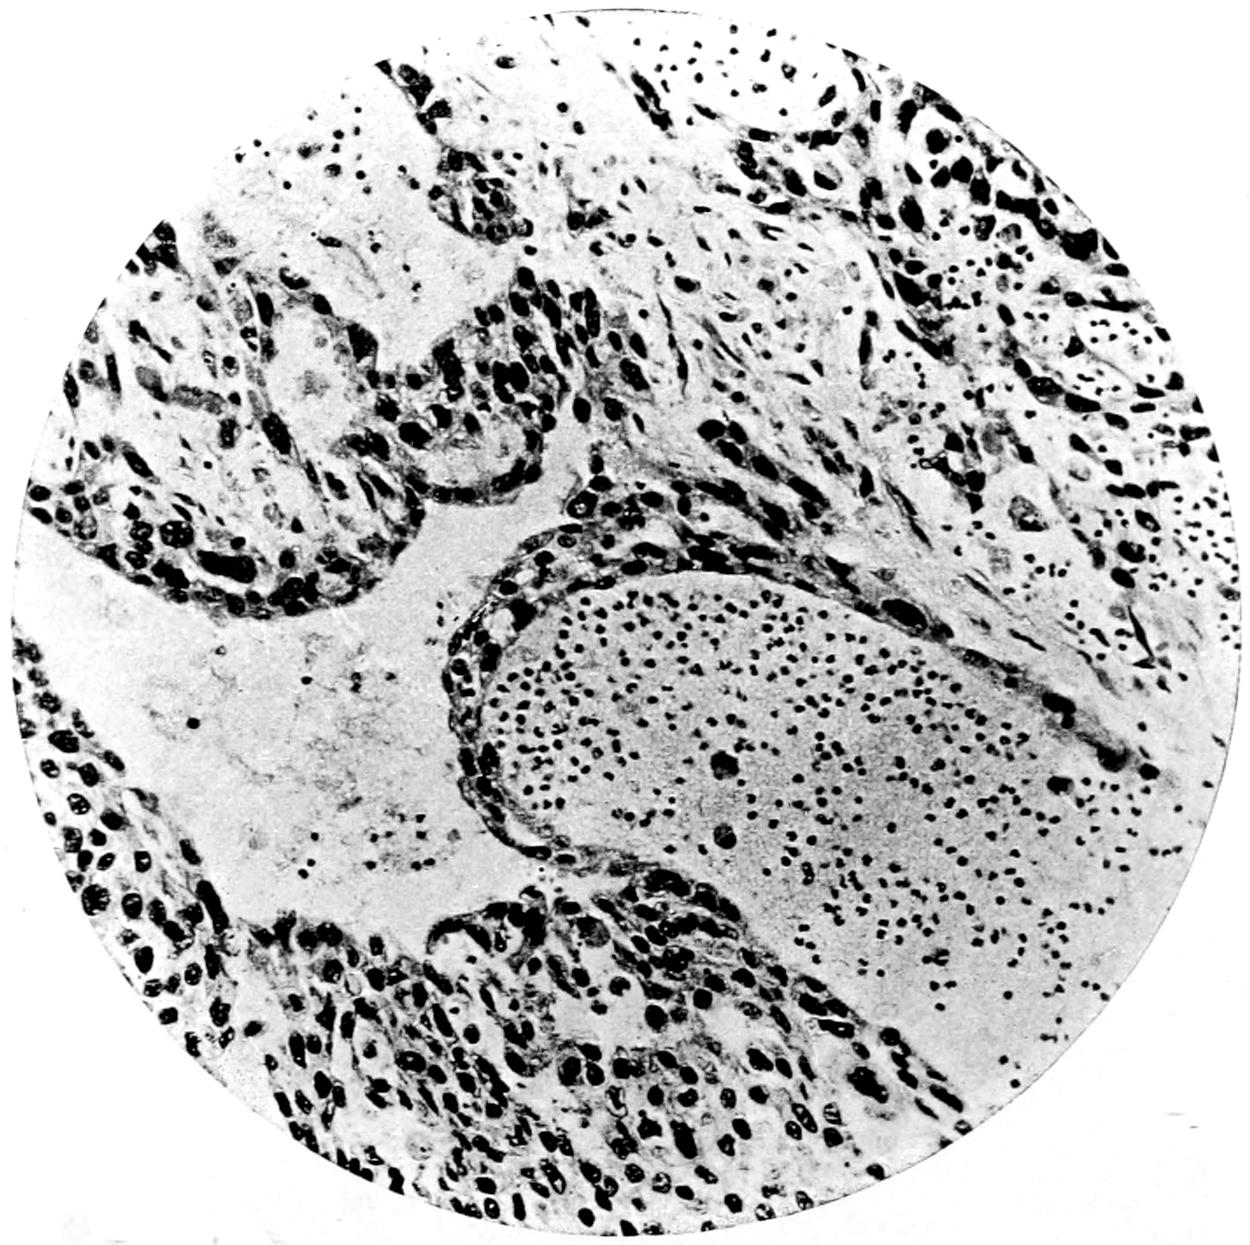

Leukocytosis is usually the rule in carcinoma, with increase in A and F; the more rapid the growth, the greater this increase. In sarcoma this is even more pronounced; when occurring without hyperinosis the probability of malignancy is greater. Non-malignant tumors produce no such changes.

The value of a careful blood examination is well illustrated by Plate I, prepared by Dr. Irving P. Lyon, in which are displayed the alterations of greatest interest to the surgeon.

Fig. I. TYPES OF LEUCOCYTES.

a. Polymorphonuclear Neutrophile. b. Polymorphonuclear Eosinophile. c. Myelocyte (Neutrophilic). d. Eosinophilic Myelocyte. e. Large Lymphocyte (large Mononuclear). f. Small Lymphocyte (small Mononuclear).

Fig. II. NORMAL BLOOD.

Field contains one neutrophile. Reds are normal.

Fig. III. ANÆMIA, POST-OPERATIVE (secondary).

The reds are fewer than normal, and are deficient in hæmoglobin and somewhat irregular in form. One normoblast is seen in the field, and two neutrophiles and one small lymphocyte, showing a marked post-hæmorrhagic anæmia, with leucocytosis.

Fig. IV. LEUCOCYTOSIS, INFLAMMATORY.

The reds are normal. A marked leucocytosis is shown, with five neutrophiles and one small lymphocyte. This illustration may also serve the purpose of showing the leucocytosis of malignant tumor.

Fig. V. TRICHINOSIS.

A marked leucocytosis is shown, consisting of an eosinophilia.

Fig. VI. LYMPHATIC LEUKÆMIA.

Slight anæmia. A large relative and absolute increase of the lymphocytes (chiefly the small lymphocytes) is shown.

Fig. VII. SPLENO-MYELOGENOUS LEUKÆMIA.

The reds show a secondary anæmia. Two normoblasts are shown. The leucocytosis is massive. Twenty leucocytes are shown, consisting of nine neutrophiles, seven myelocytes, two small lymphocytes, one eosinophile (polymorphonuclear) and one eosinophilic myelocyte. Note the polymorphous condition of the leucocytes, i. e., their variations from the typical in size and form.

Fig. VIII. VARIETIES OF RED CORPUSCLES.

a. Normal Red Corpuscle (normocyte). b, c. Anæmic Red Corpuscles. d-g. Poikilocytes. h. Microcyte. i. Megalocyte. j-n. Nucleated Red Corpuscles. j, k. Normoblasts. l. Microblast. m, n. Megaloblasts.